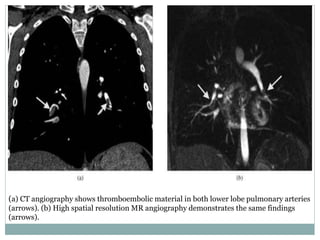

(a) CT angiography shows thromboembolic material in both lower lobe pulmonary arteries

(arrows). (b) High spatial resolution MR angiography demonstrates the same findings

(a) CT angiographyshows thromboembolic material in both lower lobe pulmonary arteries (arrows). (b) High spatial resolution MR angiography demonstrates the same findings (arrows).